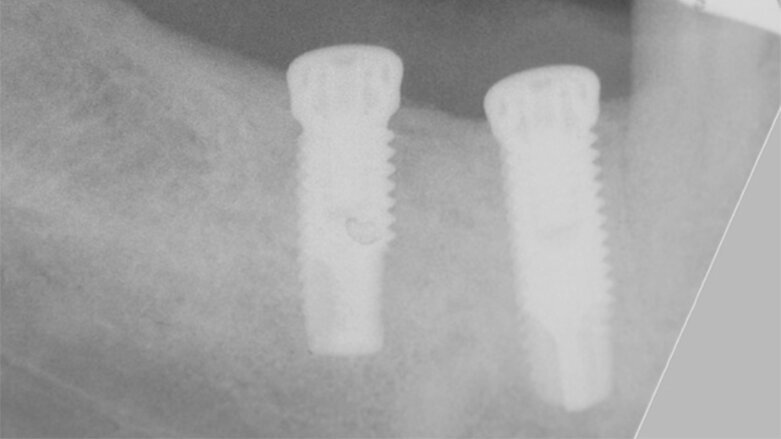

Okluzální pohled na silně atrofovaný hřeben v distální části dolní čelisti.

Okluzální pohled na tenký hřeben v distální části dolní čelisti. V oblasti keratinizované gingivy na středu hřebenu byl proveden mukoperiostální řez. Pro zajištění chirurgického přístupu byly provedeny dva rozbíhavé vertikální řezy, jeden meziobukálně od prvního premoláru a jeden šikmý vertikální řez na nejdistálnější straně krestálního řezu.